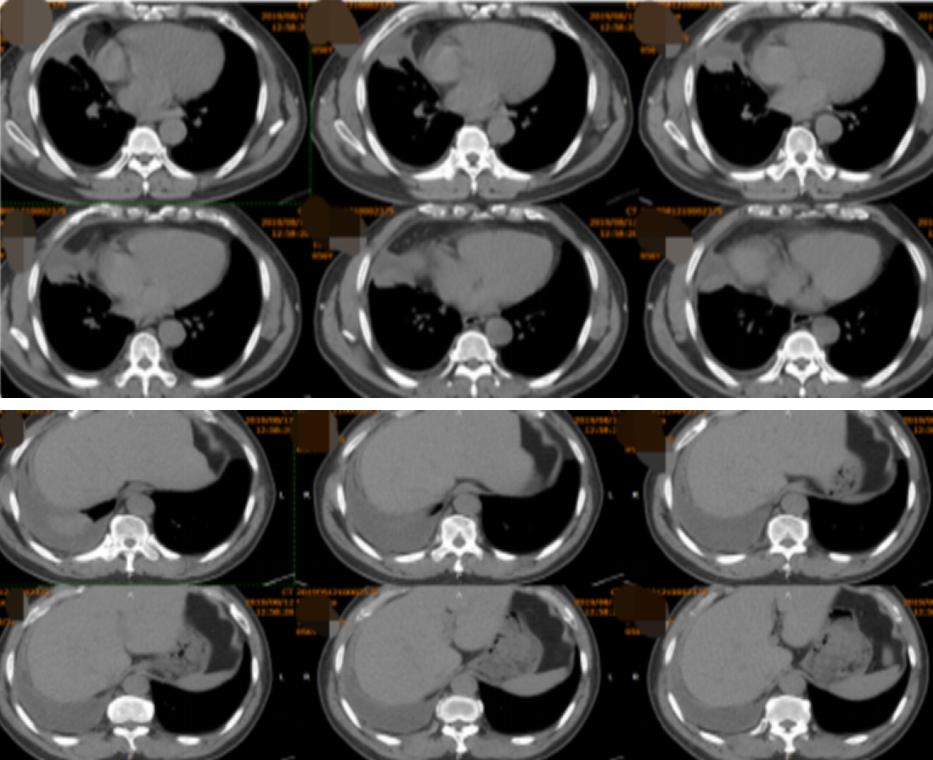

12、胸部CT:右肺中下叶团块、索条灶,右侧胸腔积液(图2)。

图2:胸部CT(2019年08月12日)

1、胸部动脉成像(CTA)(2019-08-14):右肺中下叶团块、条索灶,右侧胸腔积液,较2019-8-12老片积液增多,CTA未见明显充盈缺损(图3)。

(左 2019-08-12;右 2019-08-14)

图3:胸部动脉成像(CTA)(2019-08-14)

(从左至右)初诊、1月后、4月后:

图14:2019-09-16胸部CT(1月后):右肺中下叶团块、索条灶,右侧胸腔积液,较2019-08-14老片病灶略吸收,积液减少。2019-12-16胸部CT(4月后):右肺中下叶团块、索条灶,右侧胸腔积液,较2019-09-16老片病灶略吸收,积液减少。